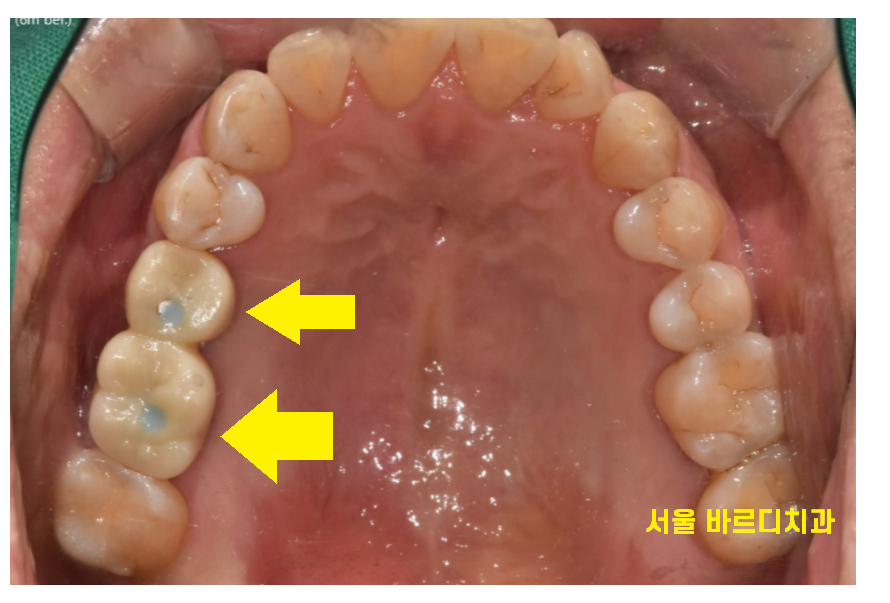

24.01.02

고덕동 임플란트 수술 후 약 4개월 뒤

보철을 올려드렸습니다.

두개의 임플란트를 묶어

튼튼하게 만들어드렸습니다.